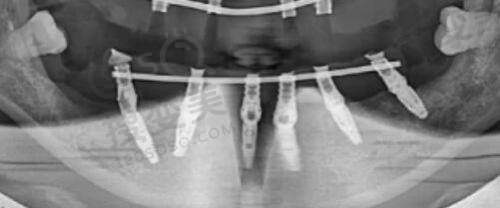

医院配备了13间层流手术室,为手术的安心提供了有力保护。同时,医院还配备了美国GE - 500彩超、西门子电视遥控X光机、德国狼牌电子腹腔镜等进口设备,这些精良的设备能够为医生提供正确的诊断和治疗依据。